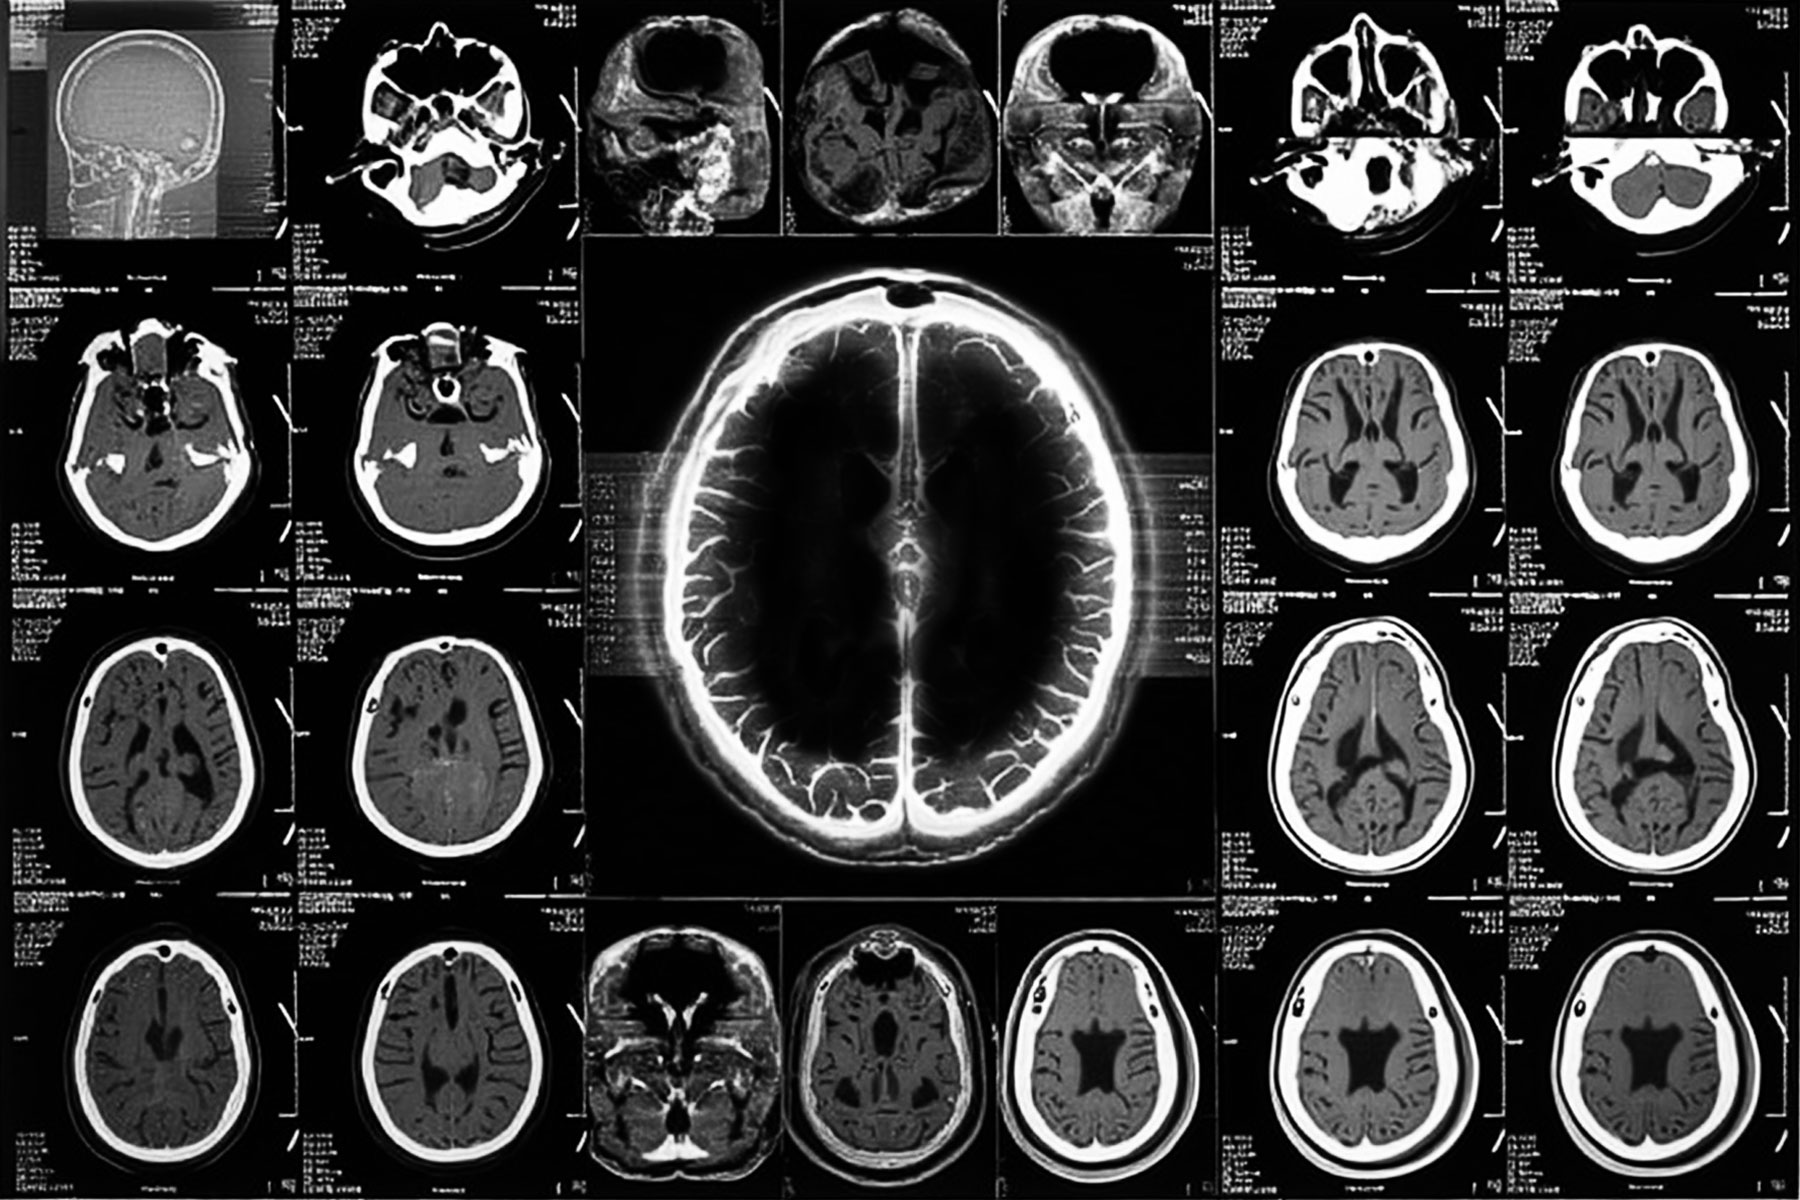

CT 이미지 속 할머니의 신체는 조용했다. 투명하게 드러난 내부, 정지된 장기와 뼈의 윤곽 사이로 검은 공동이 자리 잡고 있었다. 예상치 못한 부재. 가득 차있어야 할 머릿속이 텅 비어버린. 밀도가 낮은 부분이 검은 공동의 이미지로 나타난 순간. ‘이상 소견’은 말보다 이미지로 먼저 제시된다. 영사 기기에 뉘어진, 부피를 가진 몸이 0과 1로 이루어진 데이터로 번역된다. 납작해진다. 그 불안도 납작해진다.

현대에 이르러 엑스선을 잇는 다양한 의료영상 기법들이 개발되며 신체 투시의 범위와 정밀도는 비약적으로 확대되었다. 투명해진 몸은 불가침의 은밀한 내부를 가진 실체가 아니라 분해되고 재구성 가능한 시각데이터의 집합으로 인식되기에 이르렀다. Lisa Cartwright는 의료 영상 기술이 신체의 ‘보이지 않는 내부’를 시각화함으로써, 신체를 감각의 바깥으로 밀어내는 시각적 체계를 형성한다고 말한다. 그녀는 의료 영상 이미지가 진단 언어를 앞서 해석의 자리를 선점하고, 감각을 대신하는 새로운 지각의 질서를 만들어낸다고 보았다. 이미지는 ‘감각의 앞에 선 시각’이 되고, 그 시각은 곧 신체의 실체를 대신하게 된다.

2. The Black Cavity Revealed Within the Transparent Body

The CT image of my grandmother’s body was quiet. Inside the transparent rendering—amid the outlines of still organs and bones—a black cavity had formed. An unexpected absence. The inside of a head that should have been full appeared completely hollow. A region of low density surfaced as the image of a void. The “abnormality” arrived not in words, but through the image first. A body with volume, laid upon a scanning table, was translated into a stream of data composed of 0s and 1s. It flattened. So did the unease.

With the development of various medical imaging technologies—building upon the legacy of X-rays—the reach and precision of bodily visualization have expanded dramatically in modern times. The transparent body is no longer perceived as an untouchable, secret interior, but rather as a collection of visual data, decomposable and reconfigurable. Lisa Cartwright observes that medical imaging technologies construct a visual system that pushes the body beyond the realm of sensory perception by visualizing its “invisible interior.” According to her, these images preempt the act of diagnosis—they take the place of interpretation before language—and establish a new order of perception that displaces human senses. The image becomes a “vision that stands before sensation,” and that vision comes to substitute for the body’s material reality.